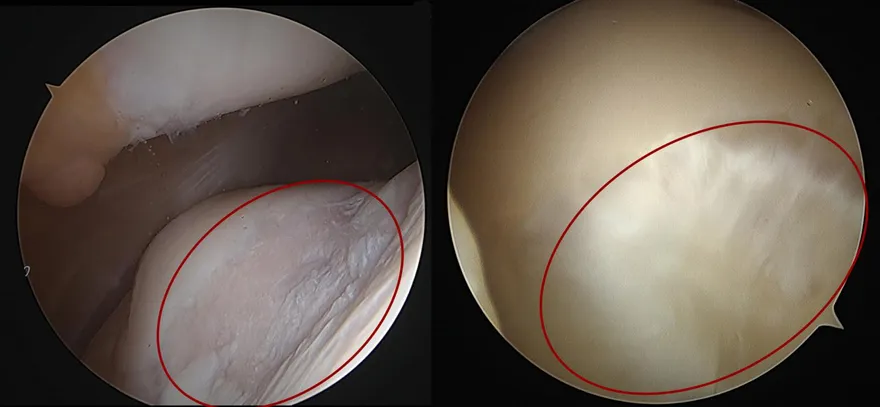

50歲女膝蓋被「挖空」痛到不行 這招讓軟骨神奇長回來!